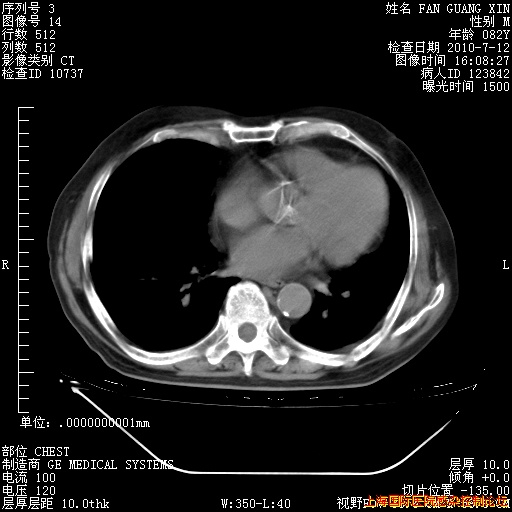

6月12日纵膈窗

整整相隔30天的肺部CT好像有所好转啊。甲强龙减量第3天,需要观察体温。

海管,自昨日你和我通完话后,不知您岳父消化道症状有无缓解?体温怎样?阅读7.12日胸部ct,个人认为目前激素治疗是有效的,甲强龙减量是适宜的。因在抗痨治疗,需密切观察肝功、肾功能和血常规。不过,老年、长期住院和大量使用激素,很担心菌群失调发生